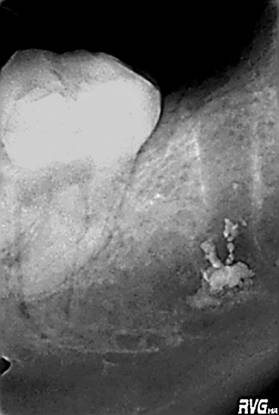

На ОРТПГ и RVG, в области отсутствующего 47зуба, наблюдается инородное тело, рентгеноконтрастное, с чёткими границами, неопределённой формы, размером 0,5/0,5 см (предположительно пломбировочный материал), находящееся в проекции нижнечелюстного канала, в области верхушки дистального корня, раннее удалённого 47зуба.

Под местной анестезией Sol.Ultracaini DS 2,5 ml, сделан разрез по переходной складке, в проекции 46, 47,48 зубов, отслоен и мобилизован слизисто-надкостничный лоскут. Сделано перфорационное отверстие в проекции верхушек корней 47зуба, размером 1.8/1.0 см, с удалением наружного кортикального и части губчатого слоя. Обнаружено наличие кусочков пломбировочного материала, при прикосновении к которым, наблюдалось свободное продвижение их по самому нижнечелюстному каналу, что в свою очередь затруднило извлечение данного пломбировочного материала. Тем не менее, под контролем микроскопа, были удалены все кусочки материала, без повреждения сосудисто-нервного пучка. Полость кости орошена изотоническим раствором, заложена гемостатическая губка, рана ушита Викрилом.